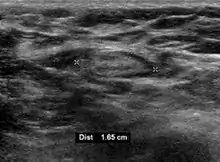

- Absence of the fatty hilum

- Increased focal cortical thickness greater than 3 cm

- Doppler ultrasonography that shows hyperaemic blood flow in the hilum and central cortex and/or abnormal (non-hilar cortical) blood flow.[25]

On ultrasound, B-mode imaging depicts lymph node morphology, whilst power Doppler can assess the vascular pattern.[27] B-mode imaging features that can distinguish metastasis and lymphoma include size, shape, calcification, loss of hilar architecture, as well as intranodal necrosis.[27] Soft tissue edema and nodal matting on B-mode imaging suggests tuberculous cervical lymphadenitis or previous radiation therapy.[27] Serial monitoring of nodal size and vascularity are useful in assessing treatment response.[27]

Lymphadenopathy of more than 1.5–2 cm increases the risk of cancer or granulomatous disease as the cause rather than only inflammation or infection. Still, an increasing size and persistence over time are more indicative of cancer.[38]